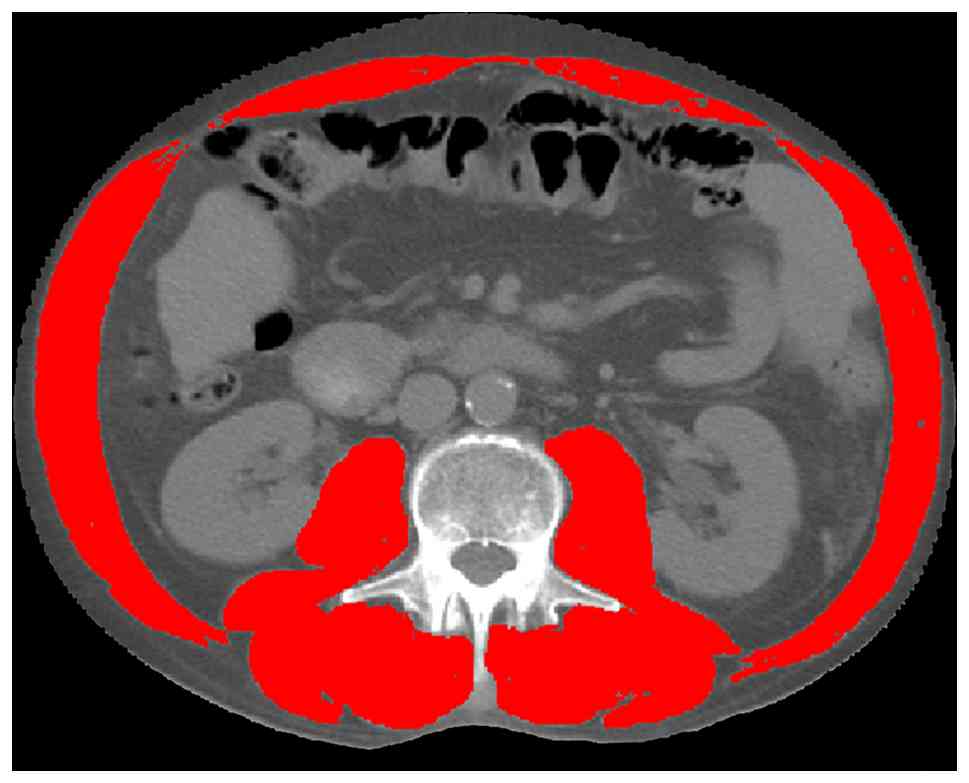

Assessment of L3-SMI

Abdominal non-contrast-enhanced CT scans were acquired on a 64-slice LightSpeed VCT scanner (GE Healthcare) with patients in the supine position. All scans used for skeletal muscle analysis were obtained within a 2-week period prior to the initiation of ICI therapy. For each scan, a single transverse image at the L3 vertebral level was selected for analysis using SliceOmatic software (version 5.0; TomoVision). Skeletal muscle area (SMA; cm2) was measured at the L3 vertebral level by segmenting muscle tissue within a Hounsfield unit window of −29 to +150, which included the psoas, erector spinae, quadratus lumborum, transversus abdominis, external and internal obliques and rectus abdominis muscles, as previously described (Fig. 1) (22). The cross-sectional SMA was automatically computed and normalized to height squared to derive the SMI (cm2/m2). All L3 SMA measurements were independently reviewed by two radiologists. In cases of disagreement, a third radiologist was consulted to reach consensus.

Cross-sectional computed tomography

images were obtained at the level of the third lumbar vertebra.

Skeletal muscle area was measured using manual tracing.

Figure 1.

Cross-sectional computed tomography images were obtained at the level of the third lumbar vertebra. Skeletal muscle area was measured using manual tracing.